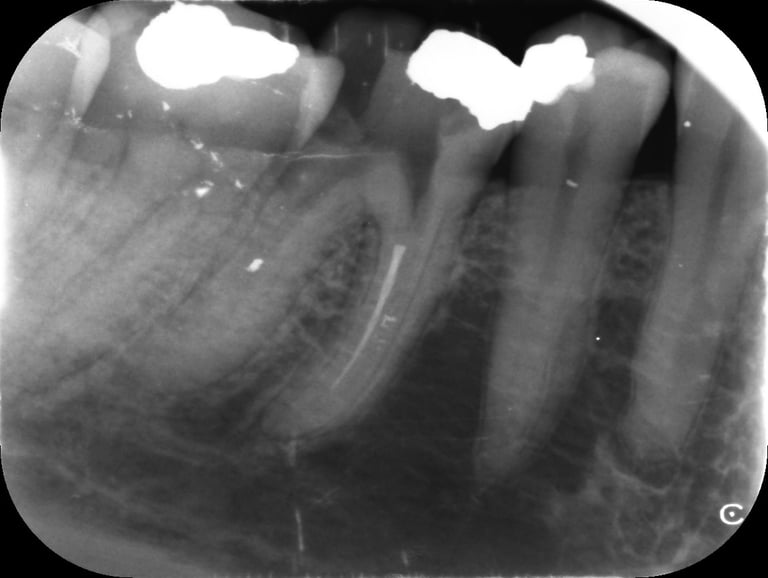

Case Study: Consent Failure in a Root Canal Treatment

We recently helped a woman who underwent a root canal at a dental practice in Bolton.

She was never warned that metal filings could break off, become embedded in her gum, or that there was a risk of ultimately losing the tooth.

All of that happened.

She experienced ongoing pain and swelling. She later told us she would never have agreed to the procedure had she been properly warned about the risks.

We made a claim against the dentist’s insurers and secured a £10,000 settlement — even though the treatment itself wasn’t negligent.